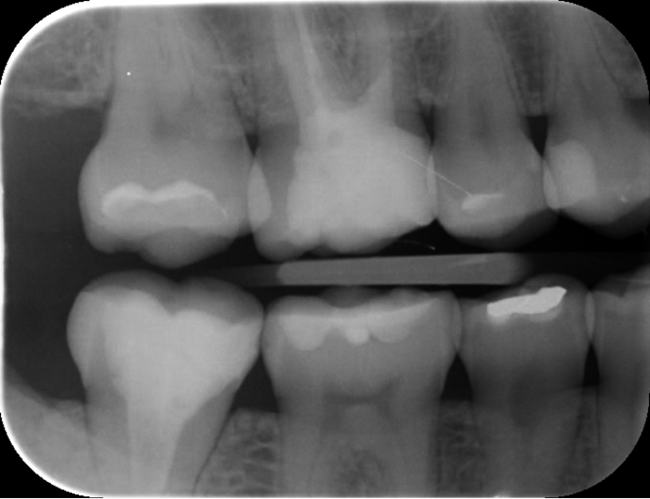

No właśnie, dlaczego nie znalazł? Nawet jeśli pracuje się z powiększeniem (lupy i mikroskop), zdiagnozowanie próchnicy na powierzchniach stycznych bywa trudne (1). Na szczęście radiografia cyfrowa w gabinetach stomatologicznych jest już powszechna. Wykonuje się dwa zdjęcia skrzydłowo-zgryzowe i gotowe (2, 3). Łatwa i przyjemna diagnostyka. Ale czy na pewno?

Spójrzmy na zdjęcia rentgenowskie. Na zdjęciu skrzydłowo-zgryzowym strony lewej (ryc. 1) bez trudu można zauważyć ubytek pod wypełnieniem na powierzchni mezjalnej zęba 25.

Ryc. 1. Zdjęcie skrzydłowo-zgryzowe strony lewej.

Gdy przyjrzymy się dokładniej, dostrzeżemy także trójkątne przejaśnienie w szkliwie na powierzchni dystalnej tego zęba i nieszczelne wypełnienie na powierzchni dystalnej zęba 35. Z kolei na zdjęciu skrzydłowo-zgryzowym strony prawej (ryc. 2) zauważalne są wypełnienia, a na powierzchniach stycznych, w obrębie szkliwa zębów 45 i 46 widać trójkątne przejaśnienia, niestety przez nałożenie punktów stycznych nie do końca pewne…

Ryc. 2. Zdjęcie skrzydłowo-zgryzowe strony prawej.

Można się zastanawiać, czy w zębie 45 dystalnie demineralizacja dotarła już do zębiny. Nie ma co liczyć, że ognisko próchnicy ulegnie remineralizacji, nawet jeśli pacjentka zacznie sumiennie oczyszczać przestrzenie międzyzębowe. Wyjście jest jedno: trzeba opracować ubytek i wykonać wypełnienie. Tylko czy można mieć pewność, że jest tam próchnica, którą należy usunąć? Czy na pewno ubytek przekroczył granicę szkliwno-zębinową?